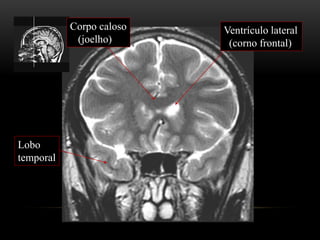

ANATOMIA TOPOGRÁFICA

Plano coronal

Giro frontal

superior

médio

inferior

Foice

inter-hemisférica

Seio sagital superior

Corpo caloso

(joelho)

Ventrículo lateral

(corno frontal)

Lobo

temporal